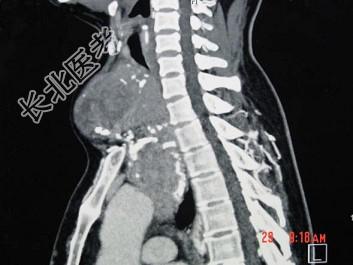

- 多项选择题女,48岁, 颈部包块3年,近来胸闷、憋气、胸痛, CT扫描如图,正确的描述或诊断是 ( )

A、胸骨后甲状腺肿

C、双侧甲状腺肿大

D、胸骨后甲状腺肿是指甲状腺50%位于胸骨后

E、胸骨后甲状腺肿是指甲状腺60%位于胸骨后